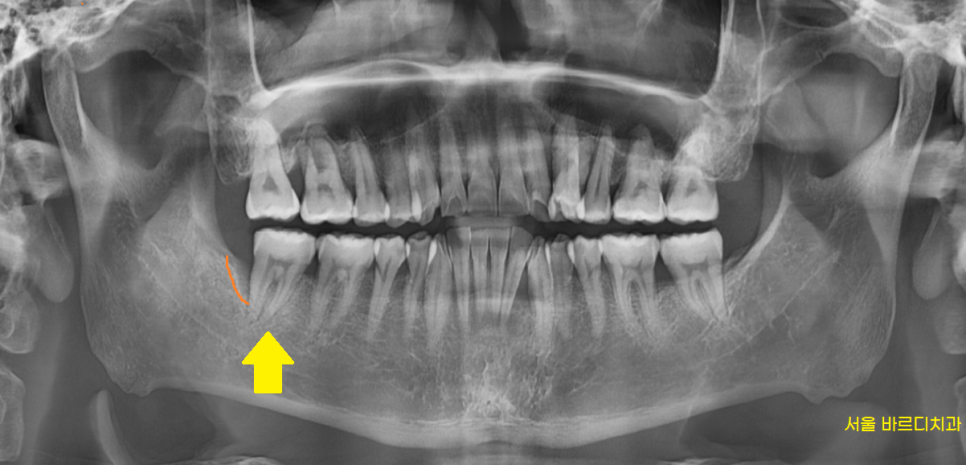

환자분께 x-ray를 찍어봐야

잇몸 뼈 상태를 알 수 있다

설명드린 후 사진을 촬영해보았습니다.

230206

잇몸 뒤쪽으로 뼈가 많이 녹았습니다.

다행히 앞쪽 뼈는 치아 뿌리를 붙잡고 있는 상황입니다.

이미 녹아버린 뼈는 재생이 안되지만

뼈가 내려가는 속도를 늦출 수는 있는데요.